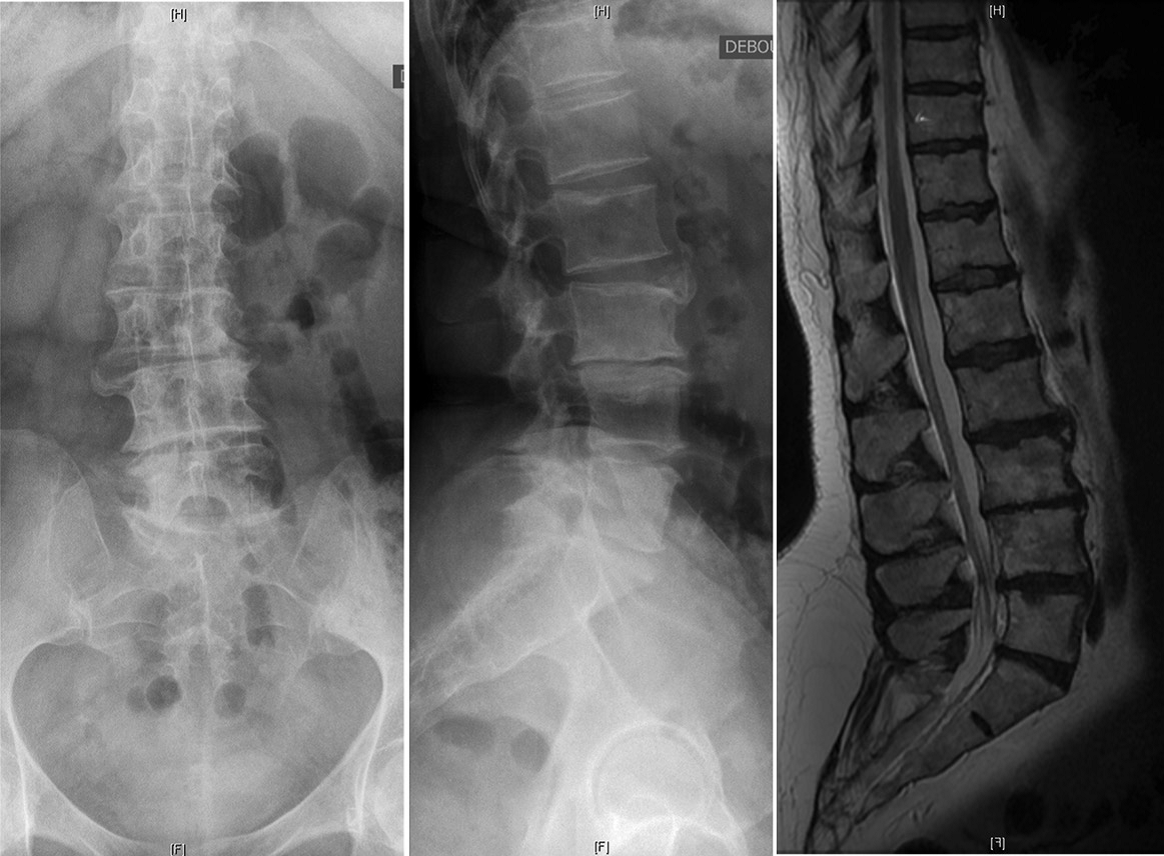

在过去的十年中,微创MIS技术治疗ASD已取得了重大进展。微创手术方式通常是通过前路腹膜后入路椎间融合器植入与后路经皮内固定相结合实现手术减压、固定及融合的目标。这种手术方式更适用于轻度到中度的ASD患者,此类患者多表现为有限节段的腰椎退行性改变和较好的弯曲柔韧性。对于MIS手术,单或双节段的退变为MIS治疗的良好手术指征,此时进行早期干预能够防止弯曲进一步的发展。目前已存在较多的文献表明通过MIS技术能够有效地矫正腰椎畸形,并且可以改善腰背痛以及神经根性疼痛。 Phan等对MIS技术治疗ASD患者进行荟萃分析后提出MIS技术的远期融合率满意且并发症发生率相对较低。Kanter等在其对MIS技术治疗ADS患者的综述中表明MIS技术在带来满意疗效的同时能够降低围手术期并发症。但是因其矫形能力有限,不建议将其应用于严重畸形的病例。

MIS技术通过结合后路经皮内固定和侧前路椎间融合器,使椎体获得重新排列,并对椎间孔狭窄进行间接减压。矢状面畸形矫正主要依靠前柱椎间隙的复位以及矢状面的腰椎前凸的恢复实现,即切除退变的椎间盘和前纵韧带以及椎间融合器的植入后节段性椎间隙高度的增加。而由椎体间隙不对称造成的冠状面畸形也可以通过椎间融合器的植入来矫正,从而使椎体终板重获平行矫正冠状面侧凸。椎间隙高度的增加与腰椎前凸的恢复使椎管与神经根管的骨性结构与软组织结构都实现了一定程度的撑开作用,从而对椎管狭窄起到了间接减压的作用。这种间接的前路减压技术可以解决开放性和封闭性半脱位,而无需对椎管进行侵入性操作。

腰椎L3-4椎间融合联合后路经皮椎弓根钉内固定。1年随访时CT显示椎间骨性融合

当然,MIS的局限性仍然是存在的。ISSG国际脊柱研究学组认为MIS技术仍然存在所谓的“天花板效应”以下情况不建议微创手术PI-LL > 20°,SVA > 9.5 cm,PT > 30°。严重的矢状面与冠状面畸形与失衡,僵硬性畸形或椎间已出现融合应通过后路开放手术解决。Mummaneni等将这一流程进行了细化,综合症状来源、冠状面和矢状面曲度、椎间盘退变程度因素将ADS分为6级。认定1-4级建议行微创手术,5-6级建议开放手术治疗。ISSG国际脊柱研究学组也曾提出基于影像特点的ADS患者手术方式的选择流程,并在2019年出版了最新修订的手术方式选择流程图。